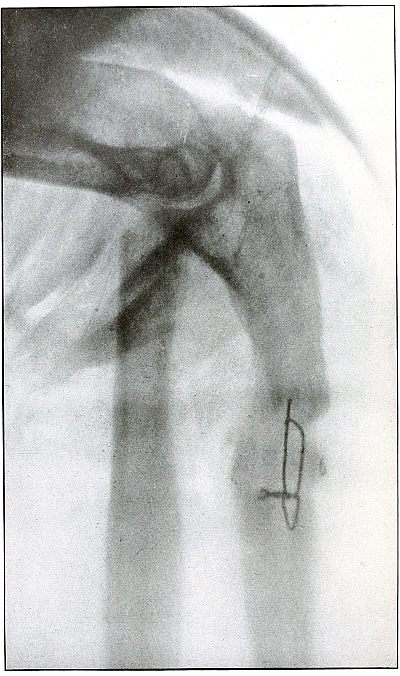

Rifle—Plate 41.

UPPER EXTREMITY.

Gunshot Fracture of the Wrist.

Wound of entrance, posterior aspect of forearm over the lower end of

the radius, with the bullet ranging forward and slightly downward to

the wound of exit and covering with great laceration the anterior

aspect of the wrist joint.

The range was close, and the energy of the high velocity of the

missile was imparted to fragments, which, becoming “secondary

missiles,” emerged with the projectile to cause extensive laceration

and destruction of tissue.

The case was received for amputation in the second week, when a grave

degree of infection extended in a cellulitis to the elbow. The ulnar

nerve and vessels were intact, but the flexor tendons were almost

entirely destroyed.

The plate, made after several weeks, when infection was under control

and after the end of the radius and fragments of the carpus had been

informally removed, shows a rarefaction of the carpus and proximal

ends of the metacarpus, due to infection and disuse.

Frequent incisions and extension of drainage, with removal of detached

fragments, was continued for several months. The wound was closed in

the sixth month, with ankylosis and deformity of the wrist,

as shown in plate 42.